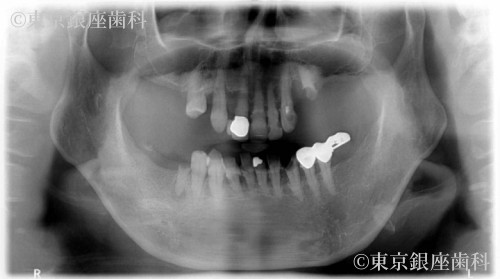

Before

疾患 歯周病

重度歯周病で上下インプラントを選択。治療後、顔の赤みが改善し噛む機能も回復。補綴の形態修正も行い自然で快適な仕上がりに。